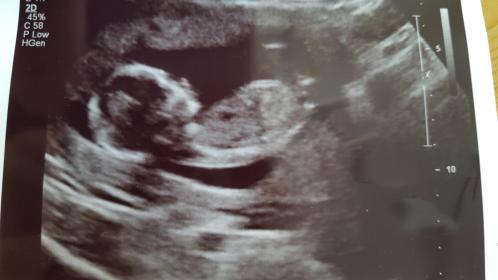

This is from My 14 week scan and the tech didnt want to

Talk about the gender of the baby.

İ really want it to be a girl so i Hope You can help me with the guessing 😊😊

Tricky, I don't think the nub is properly visible in these pics. Do you have more, or a video or a potty shot?

That last pic *might* be showing a girly nub, but I really don't want to give you too much hope. You could post the other pics if you have any more, you never know if there is a better nub shot among them.